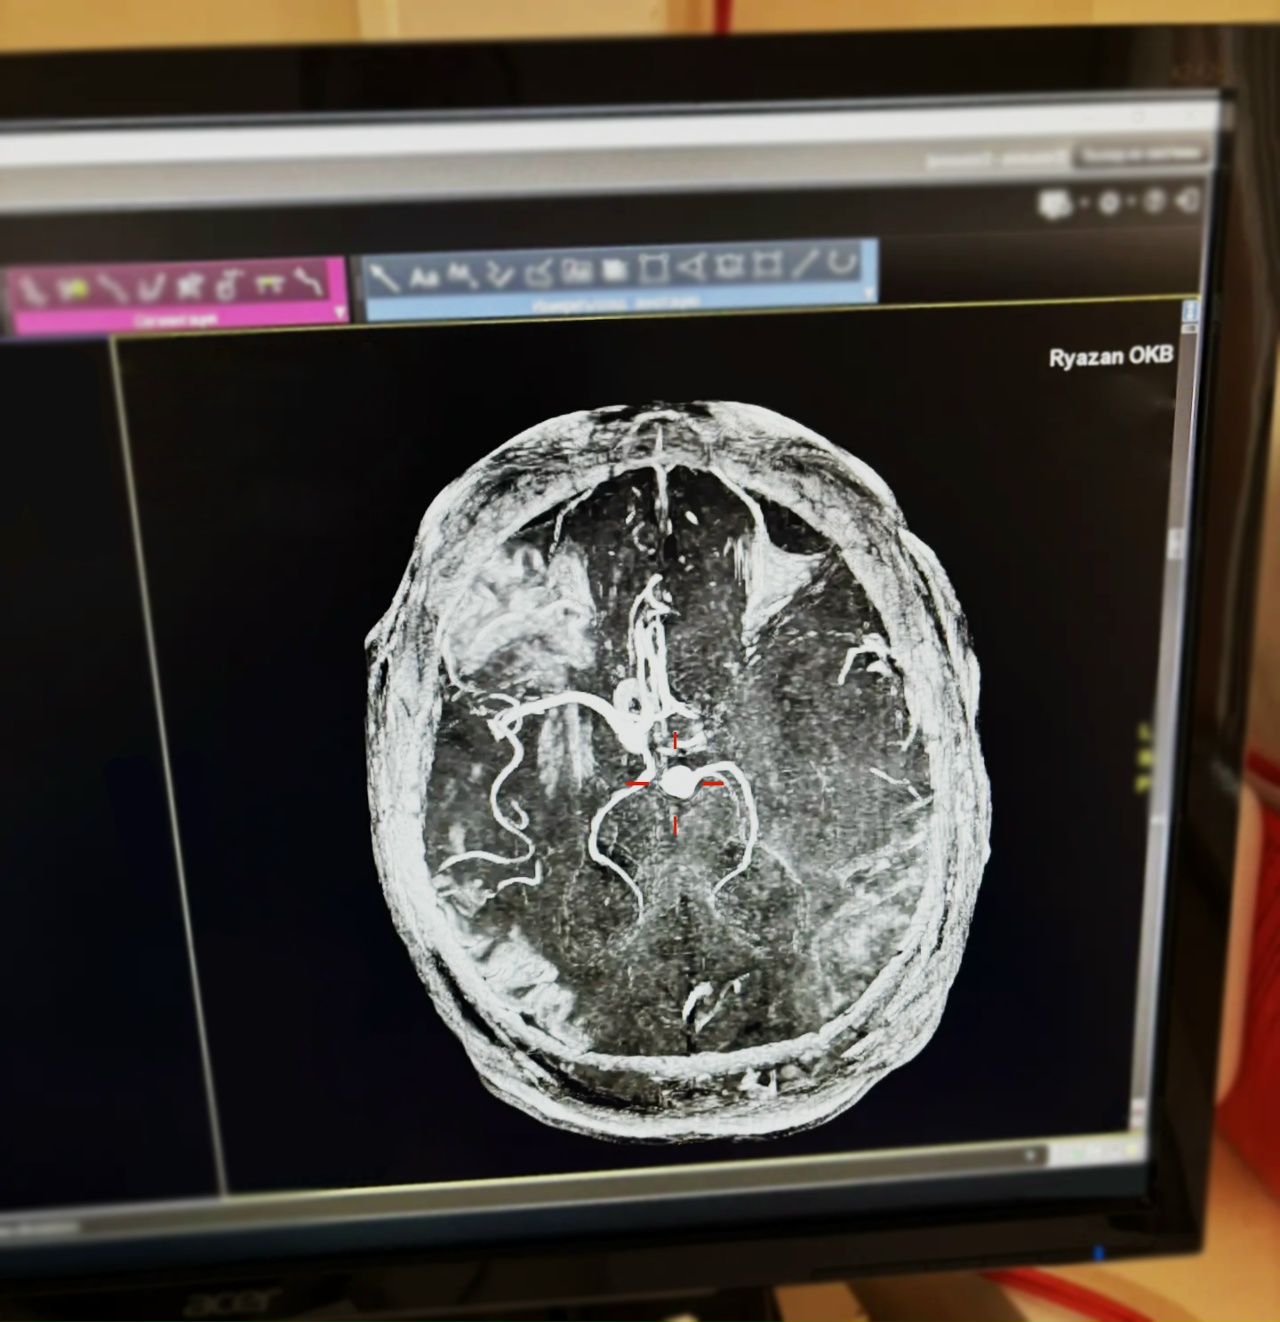

Врачи применили тромболитическую терапию, которая позволяет растворить тромб и восстановить кровоток. Состояние мужчины стабилизировалось за 5 дней.